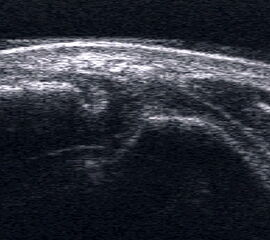

Peronealsehnenluxation. TS an der Fibulaspitze. Die Sehnen sind über die Fibula gerutscht.

Abbildung 45

Lagerung: Rückenlage, Innendrehung des Beins.

Schnittführung: TS und LS hinter dem Außenknöchel.

Referenzstrukturen: Fibulaspitze, Sehnen der Mm. peronaei.

Befunde: Halo-Phänomen. Bei der Luxation rutschen die Sehnen über den Außenknöchel nach lateral/ventral. Eine spontane Reposition unter Entspannung ist möglich. Im TS kann die Instabilität ggf. mittels Provokationstest durch Eversion gegen Widerstand sonographisch dynamisch dargestellt werden. Bei der Diagnostik der Peronealsehnen Instabilität oder Luxation ist die Sonographie durch die Möglichkeit der dynamischen Untersuchung dem MRT klar überlegen 4.